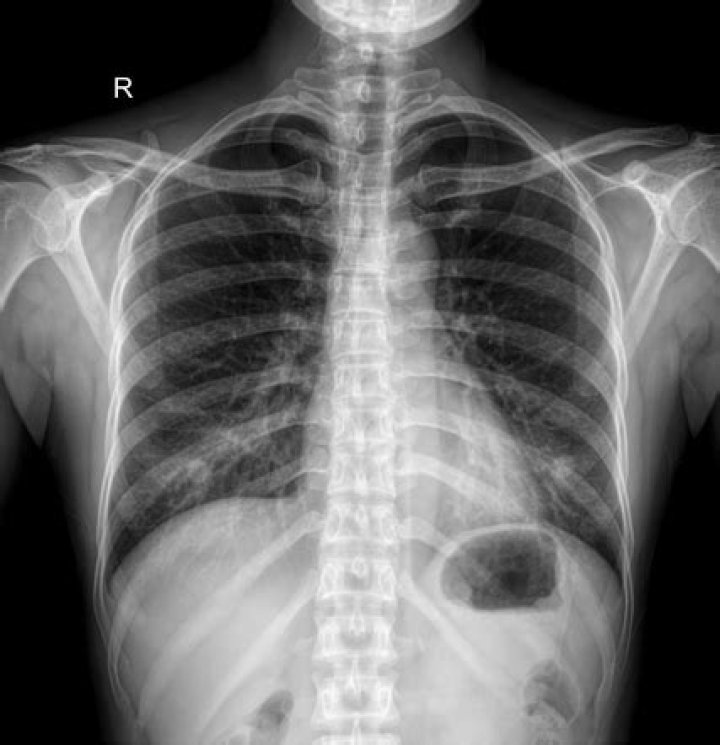

Nipple shadows refer to the silhouettes of the nipples on frontal chest radiographs, which may mimic solitary pulmonary nodules (SPNs).Click to see full answer. Also question is, are nipple shadows common?Nipple Shadows on Chest X-Rays. Nipple shadows are apparent on approximate 10% of AP/PA views of the chest. Nipple shadows can be seen in patients with different genders and age. When present, they need to be differentiated from more significant intra thoracic pleural or pulmonary nodules.Furthermore, what is bilateral nipple shadows? Nipple shadows are often seen on chest x-rays and can be easily confused for a pulmonary nodule or nodules. If there is any doubt the easiest method of determining whether opacities represent nipple shadows is a repeat chest x-ray with nipple markers. Hereof, what are nipple markers? Nipple markers. These can be small ball-bearings, paperclips reformed in triangle shapes around the nipple or other radiopaque markers, which are stuck to the chest with the nipple within or with the marker directly on the nipple.What does it mean if you have a shadow on your lung?Pulmonary edema is a condition involving the accumulation of fluid in the lungs, often due to heart disease. Aortic aneurysm (an enlargement of the aorta as it leaves the heart or begins to descend through the chest) can cause a shadow on chest X-rays.